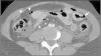

Varón de 31 años trasladado a urgencias de nuestro hospital por politraumatismo tras accidente de tráfico. Se realizó TC «total body» en donde se apreció hemoperitoneo, escaso neumoperitoneo y engrosamiento difuso de asas intestinales (fig. 1). Existía ausencia de realce tras contraste intravenoso (CIV) de un asa yeyunal, compatible con hipoperfusión (fig. 2) y focos de perforación intestinal (fig. 1). Se realizó cirugía urgente que confirmó el asa isquémica tras avulsión de vasos mesentéricos de pequeño calibre. La avulsión de los vasos mesentéricos por traumatismo abdominal cerrado es una entidad infrecuente, en especial sin lesión de víscera sólida asociada. Aunque el hematoma mesentérico o el extravasado de CIV son signos más específicos, debe sospecharse ante un segmento intestinal con pared engrosada e hipoperfundida, neumoperitoneo y hemoperitoneo sin lesión de víscera sólida.